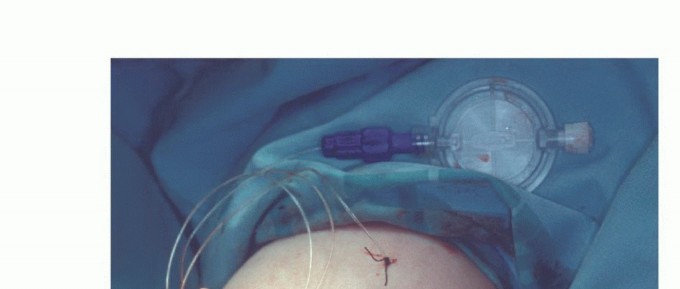

- بعد التأكد من إيقاف النزيف، يتم وضع أنبوب تصريف (Drain) لمنع تجمع السوائل.

- تُخاط طيات الجلد فوق العظم والعضلات المشكلة بعناية فائقة.

- يتم تطبيق ضماد معقم.